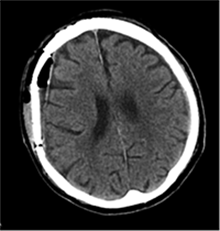

53 m. vyras sumuštas gatvėje ir greitosios medicinos pagalbos atvežtas į Priėmimo skyrių. Pacientui atlikta galvos kompiuterinė tomografija (GKT). Rasta: poūmė, stora, apie 16 mm dydžio subdurinė hematoma (SDH) dešinėje pusėje konveksitaliai ir ūmi nedidelė SDH kairėje pusėje frontoparietaliai. Vidurio struktūrų dislokacija (VSD) į kairę – minimali. Kairėje – kaukolės skliauto linijinis lūžis. Nustatyta nosies kaulų, nosies pertvaros, dešiniojo viršutinio žandikaulio kaktinės ataugos ir kūno, sinuso sienelių lūžių, dešinės akiduobės medialinio krašto lūžių ir dešiniojo skruostinio lanko lūžių (1 pav.). 2020 m. liepos mėn. pacientas skubos tvarka operuotas: atlikta dešinė kraniotomija, pašalinta hematoma. Atlikus kontrolinę GKT, buvo matyti, kad pašalinta didžioji hematomos dalis (2 pav.). Pacientas konsultuotas veido ir žandikaulio chirurgo, skubus chirurginis gydymas neindikuotas. Praėjus 3 savaitėms, pacientas, esant gerai funkcinei ir neurologinei būklei, tolesnio gydymo perkeltas į slaugos ligoninę, vėliau išleistas gydytis ambulatoriškai.

2 pav. Po pirmosios operacijos (didžioji hematomos dalis pašalinta, VSD be dislokacijos)